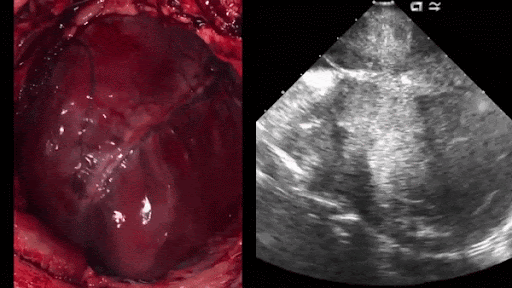

As a student doctor, I have seen many patients who had cancers growing in their bodies and don’t feel it and don’t have any symptoms until it is too late (until the tumor has metastasized to other organs) I have seen a patient who has lymphoma (a type of blood cancer) He didn’t feel anything; he literally had no symptoms, but one day he started to have some symptoms related to his respiratory system like cough, dyspnea, hemoptysis. When he did a chest x-ray, he was found to have massive pleural effusion (water on the lung) due to the tumor metastasized to his lung. He had an x-ray similar to that. Look at the left lung! Not only that but he also, when he was asked to do a CT scan on his abdomen, he was found to have the tumor metastasized to his liver. (Can you see these blackish areas? These are multiple tumor masses growing at his liver) I knew that this patient had a very bad prognosis and he most likely will pass away in a few months. It is very sad to know that. The...